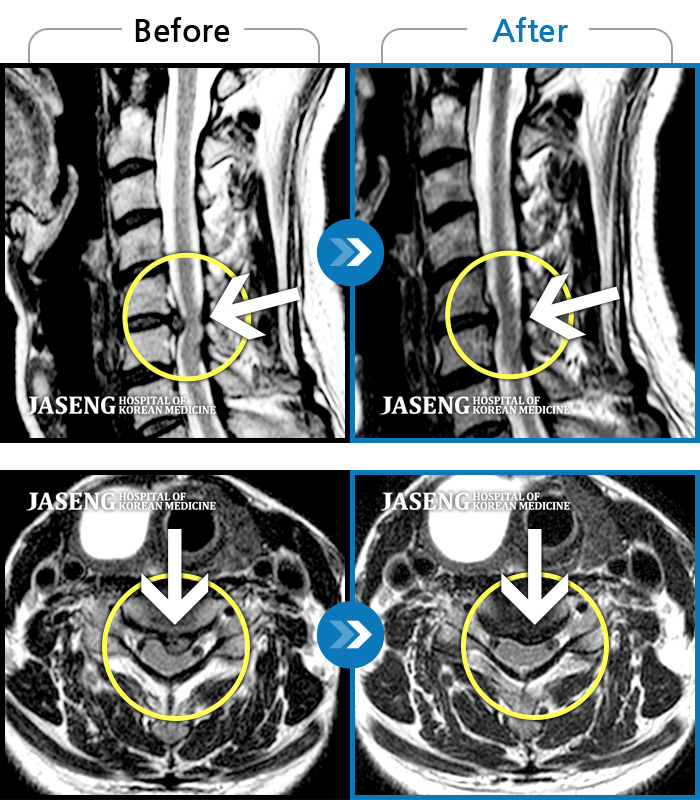

허리디스크

많이 본 사례

강남 · 박종훈 원장

허리와 양쪽 엉덩이 통증 및 좌측 둔부, 대퇴, 소퇴 후면부 통증 및 저림

촬영시기

2013.05.14 ~ 2014.04.23

2014.05.07

조회수 55,357